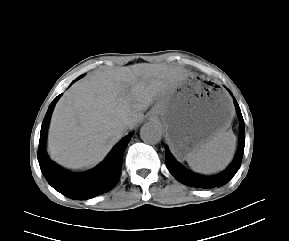

标题: CT19533:病变来源于哪?

患者,男,发现上腹部包块两月余。

病变位于肝胃间隙,实际就是位于小网膜囊(左肝下后间隙),呈轻度不均匀性强化,腹腔内及腹膜后见多发肿大淋巴结。所以我考虑肝胃间隙恶性胃肠间质瘤并淋巴结转移。

病灶强化不显著,灶周及腹膜后见多量淋巴结肿大,考虑淋巴瘤可能,其次考虑间质瘤

病灶与胰腺分界不清,来源于胰腺?

强化后病变与胃壁分界清楚,并且血供不是来源胃壁血管。考虑胰腺颈体癌并腹腔腹膜后淋巴结转移。